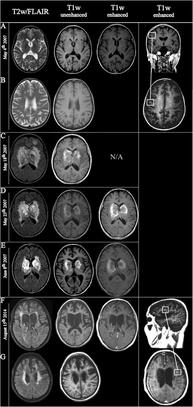

| Fulminating ADEM showing many lesions. The patient survived, but remained in a persistent vegetative state | |

ADEM produces multiple inflammatory lesions in the brain and spinal cord, particularly in the white matter. Usually these are found in the subcortical and central white matter and cortical gray-white junction of both cerebral hemispheres, cerebellum, brainstem, and spinal cord,[16] but periventricular white matter and gray matter of the cortex, thalami and basal ganglia may also be involved.